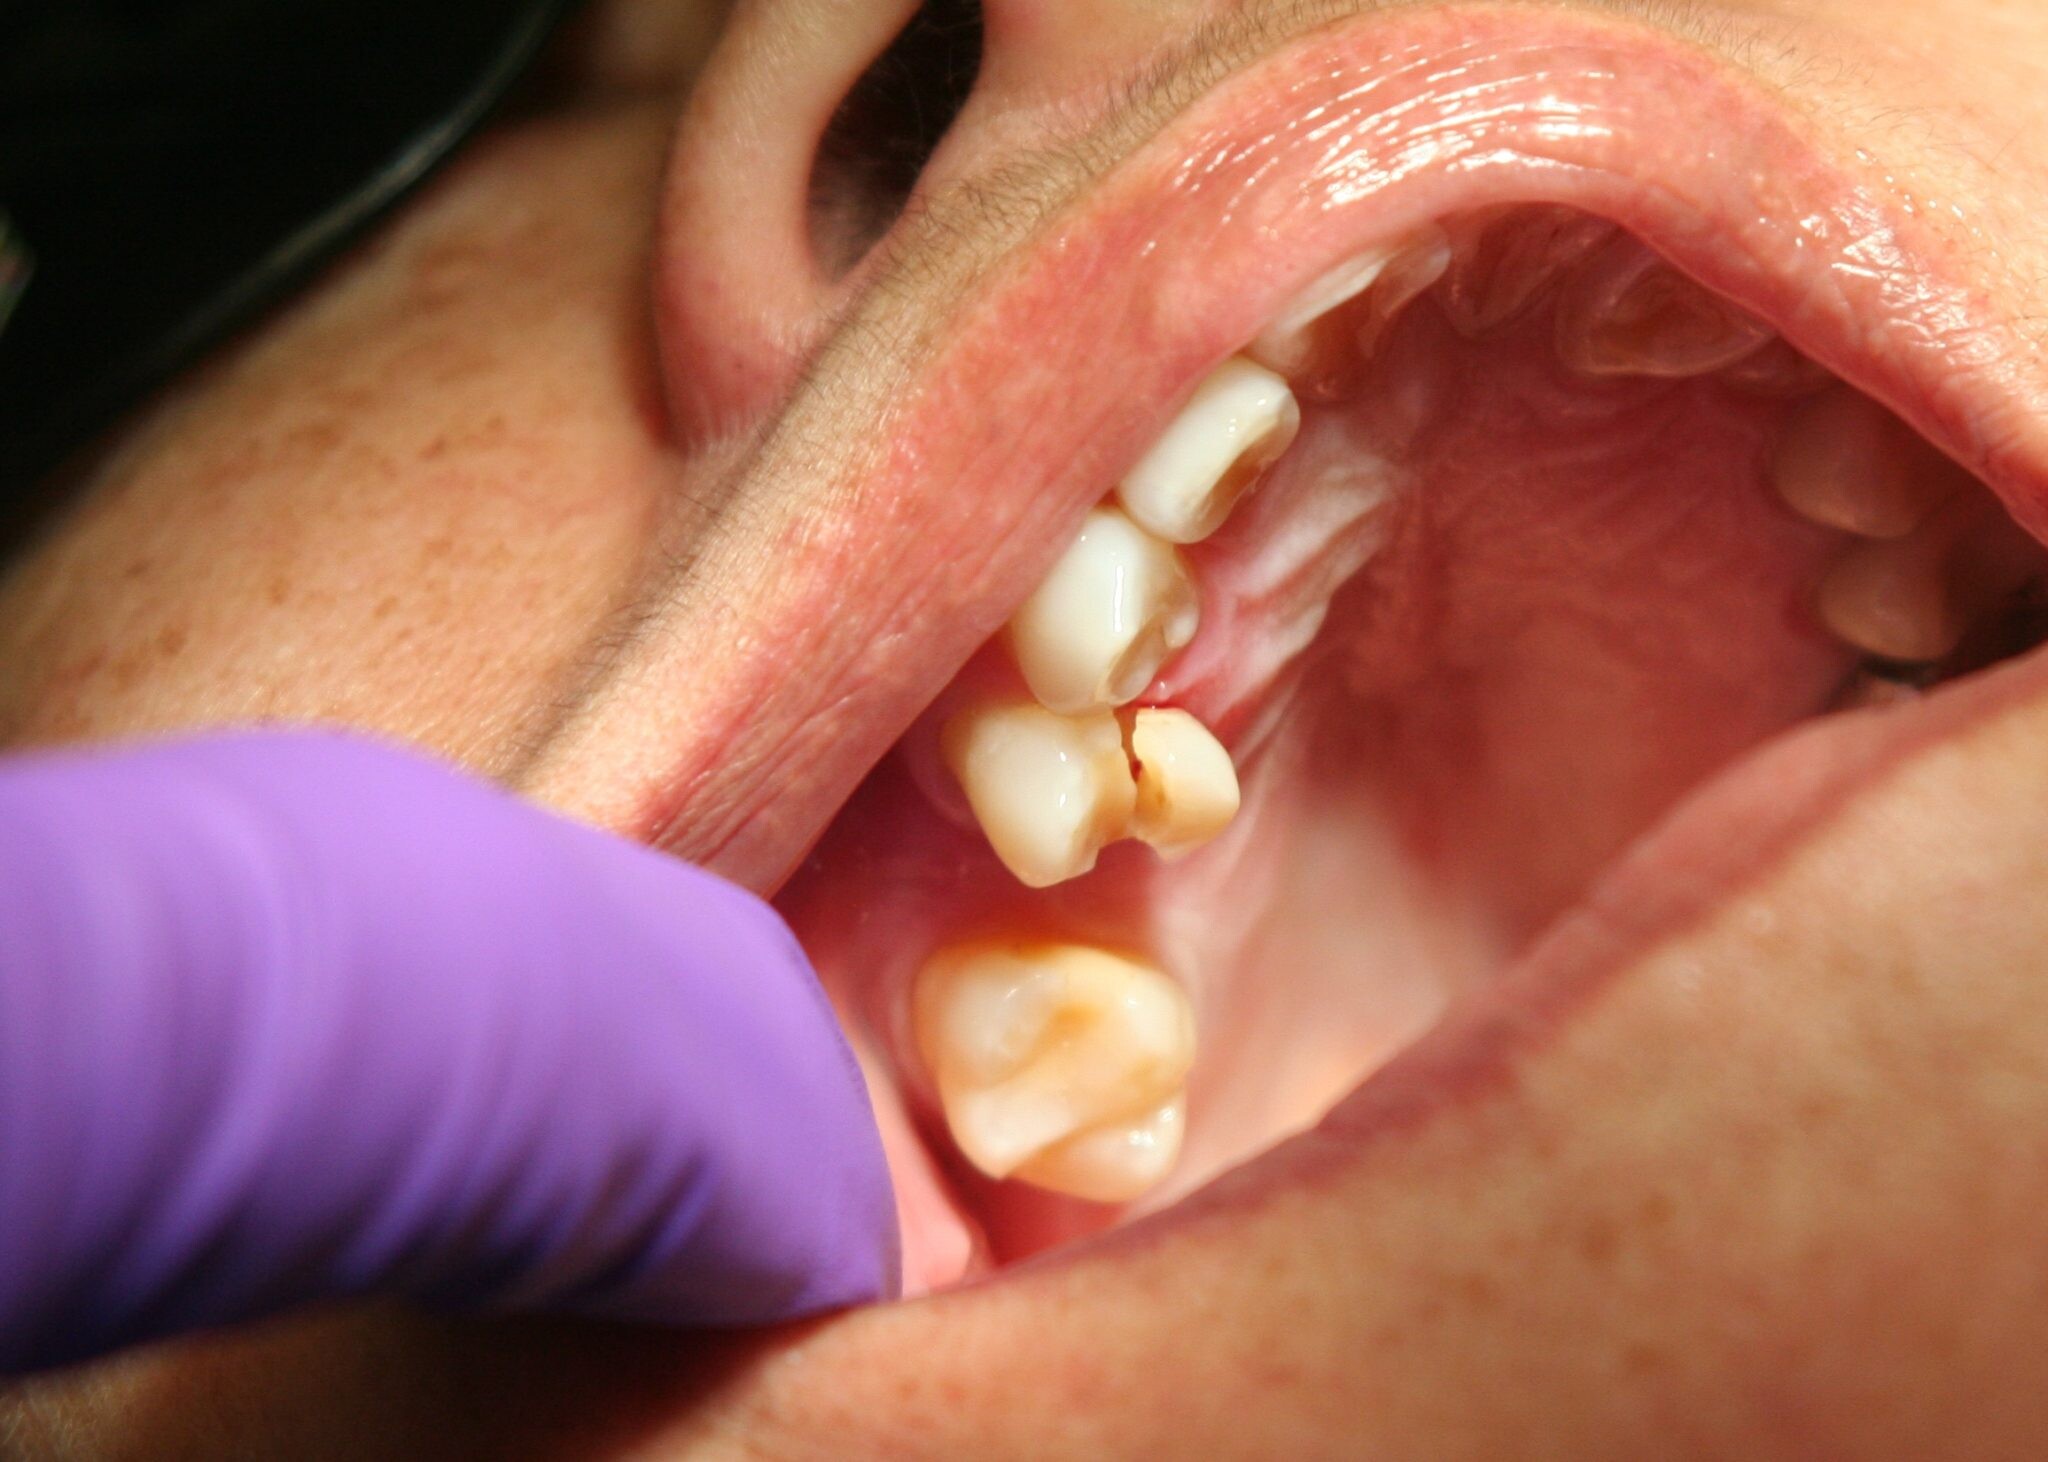

Cavities are pretty common. As the National Institutes of Health points out, the only condition more common than a cavity is the common cold. If you've never experienced tooth decay, you might wonder, "What does a cavity feel like?" The answer depends on the stage of the cavity and what foods you eat. Some foods, such as sweets, might trigger the pain of a cavity more than others.

How Cavities Form

Your mouth is naturally full of germs. Some of those germs are perfectly healthy, but others can be harmful. When you eat something sugary, such as candy or even potato chips, or drink a sugary beverage, the germs feed on the sugars in the substance. This produces acid, which is strong enough to wear away tooth enamel if not cleaned off quickly enough. In the end, a dental cavity begins to form.

In the early stages, a cavity can be reversed, as the National Institute of Dental and Craniofacial Research notes. Brushing your teeth with a toothpaste that contains fluoride can help restore the enamel and reverse the effects of cavities.

Signs of a Cavity

What does a cavity feel like? In the earliest stages, the answer might be nothing. There are no nerves in your tooth enamel, so when the decay is in that layer, you likely won't feel a thing. Once the decay has progressed enough to reach the softer tissues inside the tooth, where the dentin and nerves are, you might notice signs of a cavity. Your teeth might feel sensitive and you could feel some pain, especially after eating sweets, hot foods or cold foods. The pain can be fairly mild or sharp and intense. Some people with cavities also feel pain when biting down.

Depending on the size of the cavity, you may be able to see evidence of it in your mouth. Cavities sometimes create visible holes in the teeth. They can also create stains that are black, brown or white on the surface of the tooth.

Cavities and Sweets

Why are you more likely to feel pain from a cavity when you eat sweets? Some foods, including sweets, are more likely to cause pain when there is enamel erosion. Sweet foods tend to be sticky, so they often cling to your teeth. The germs that feed on them can then produce more acid, which can make its way into the cavity, irritating the nerves. Even if you don't have a cavity, sugary foods will cause more sensation in sensitive teeth.

Seeing Your Dentist

What should you do if you think you have a cavity? The first step is to see your dentist. Although cavities can be reversed in the early stages, by the time you are feeling discomfort or pain, only a dentist can treat them. An x-ray will be taken to determine how the cavity has progressed into the tooth. Depending on how severe the cavity is, you might need a filling to fix it. If the decay is very severe, the dentist might replace the tooth with a crown or perform a root canal.

Even if you're not sure if you have a cavity, regular professional cleaning and dental visits are important. A dental hygienist can apply a fluoride treatment to help strengthen the teeth and reverse the very early stages of decay. He or she can also give you tips on the best ways to brush your teeth and advise you about what foods to avoid or consume less frequently to reduce your risk for cavities. As with many conditions, when it comes to cavities, taking preventative steps is a lot easier than treating the problem down the road.